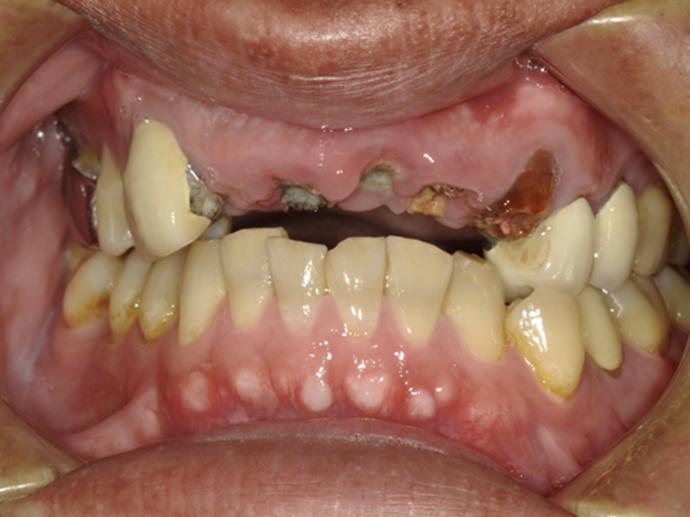

ALL ON全口重建是由4-6 顆植體(依條件而定)成,專為多顆缺牙或全口無牙患者設計的創新全口重建技術,僅需4-6 支植體即可支撐一整排固定式假牙,大幅減少手術次數與成本,並縮短療程時間。

適用無牙或重度牙周病患者